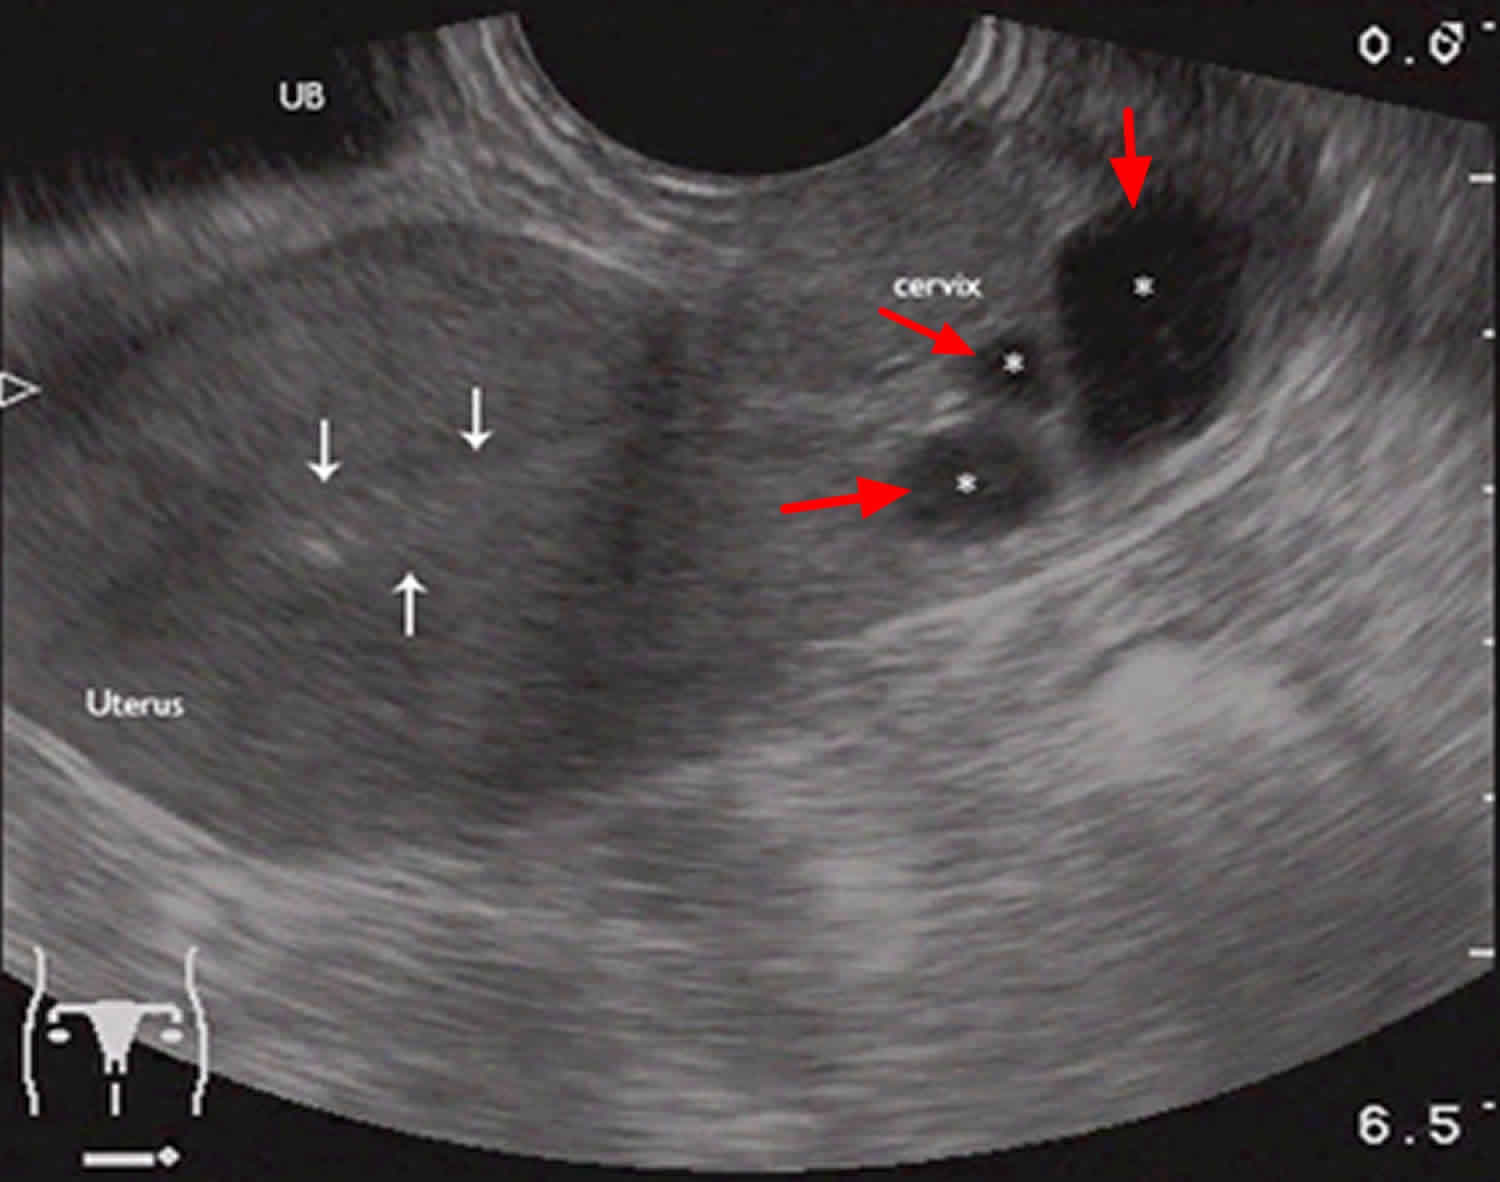

Ruptured ovarian cyst Critical Care Sonography What Happens When A Cyst Ruptures In Uterus A sudden, sharp pain in the lower abdomen, with nausea and vomiting in some cases, can indicate a ruptured cyst. The larger the cyst, the greater the risk. Diagnosing a ruptured ovarian cyst. What is a ruptured ovarian cyst? When you ovulate, the cyst or follicle that holds the egg “ruptures” to release the egg. Ovarian cysts are not uncommon.. What Happens When A Cyst Ruptures In Uterus.